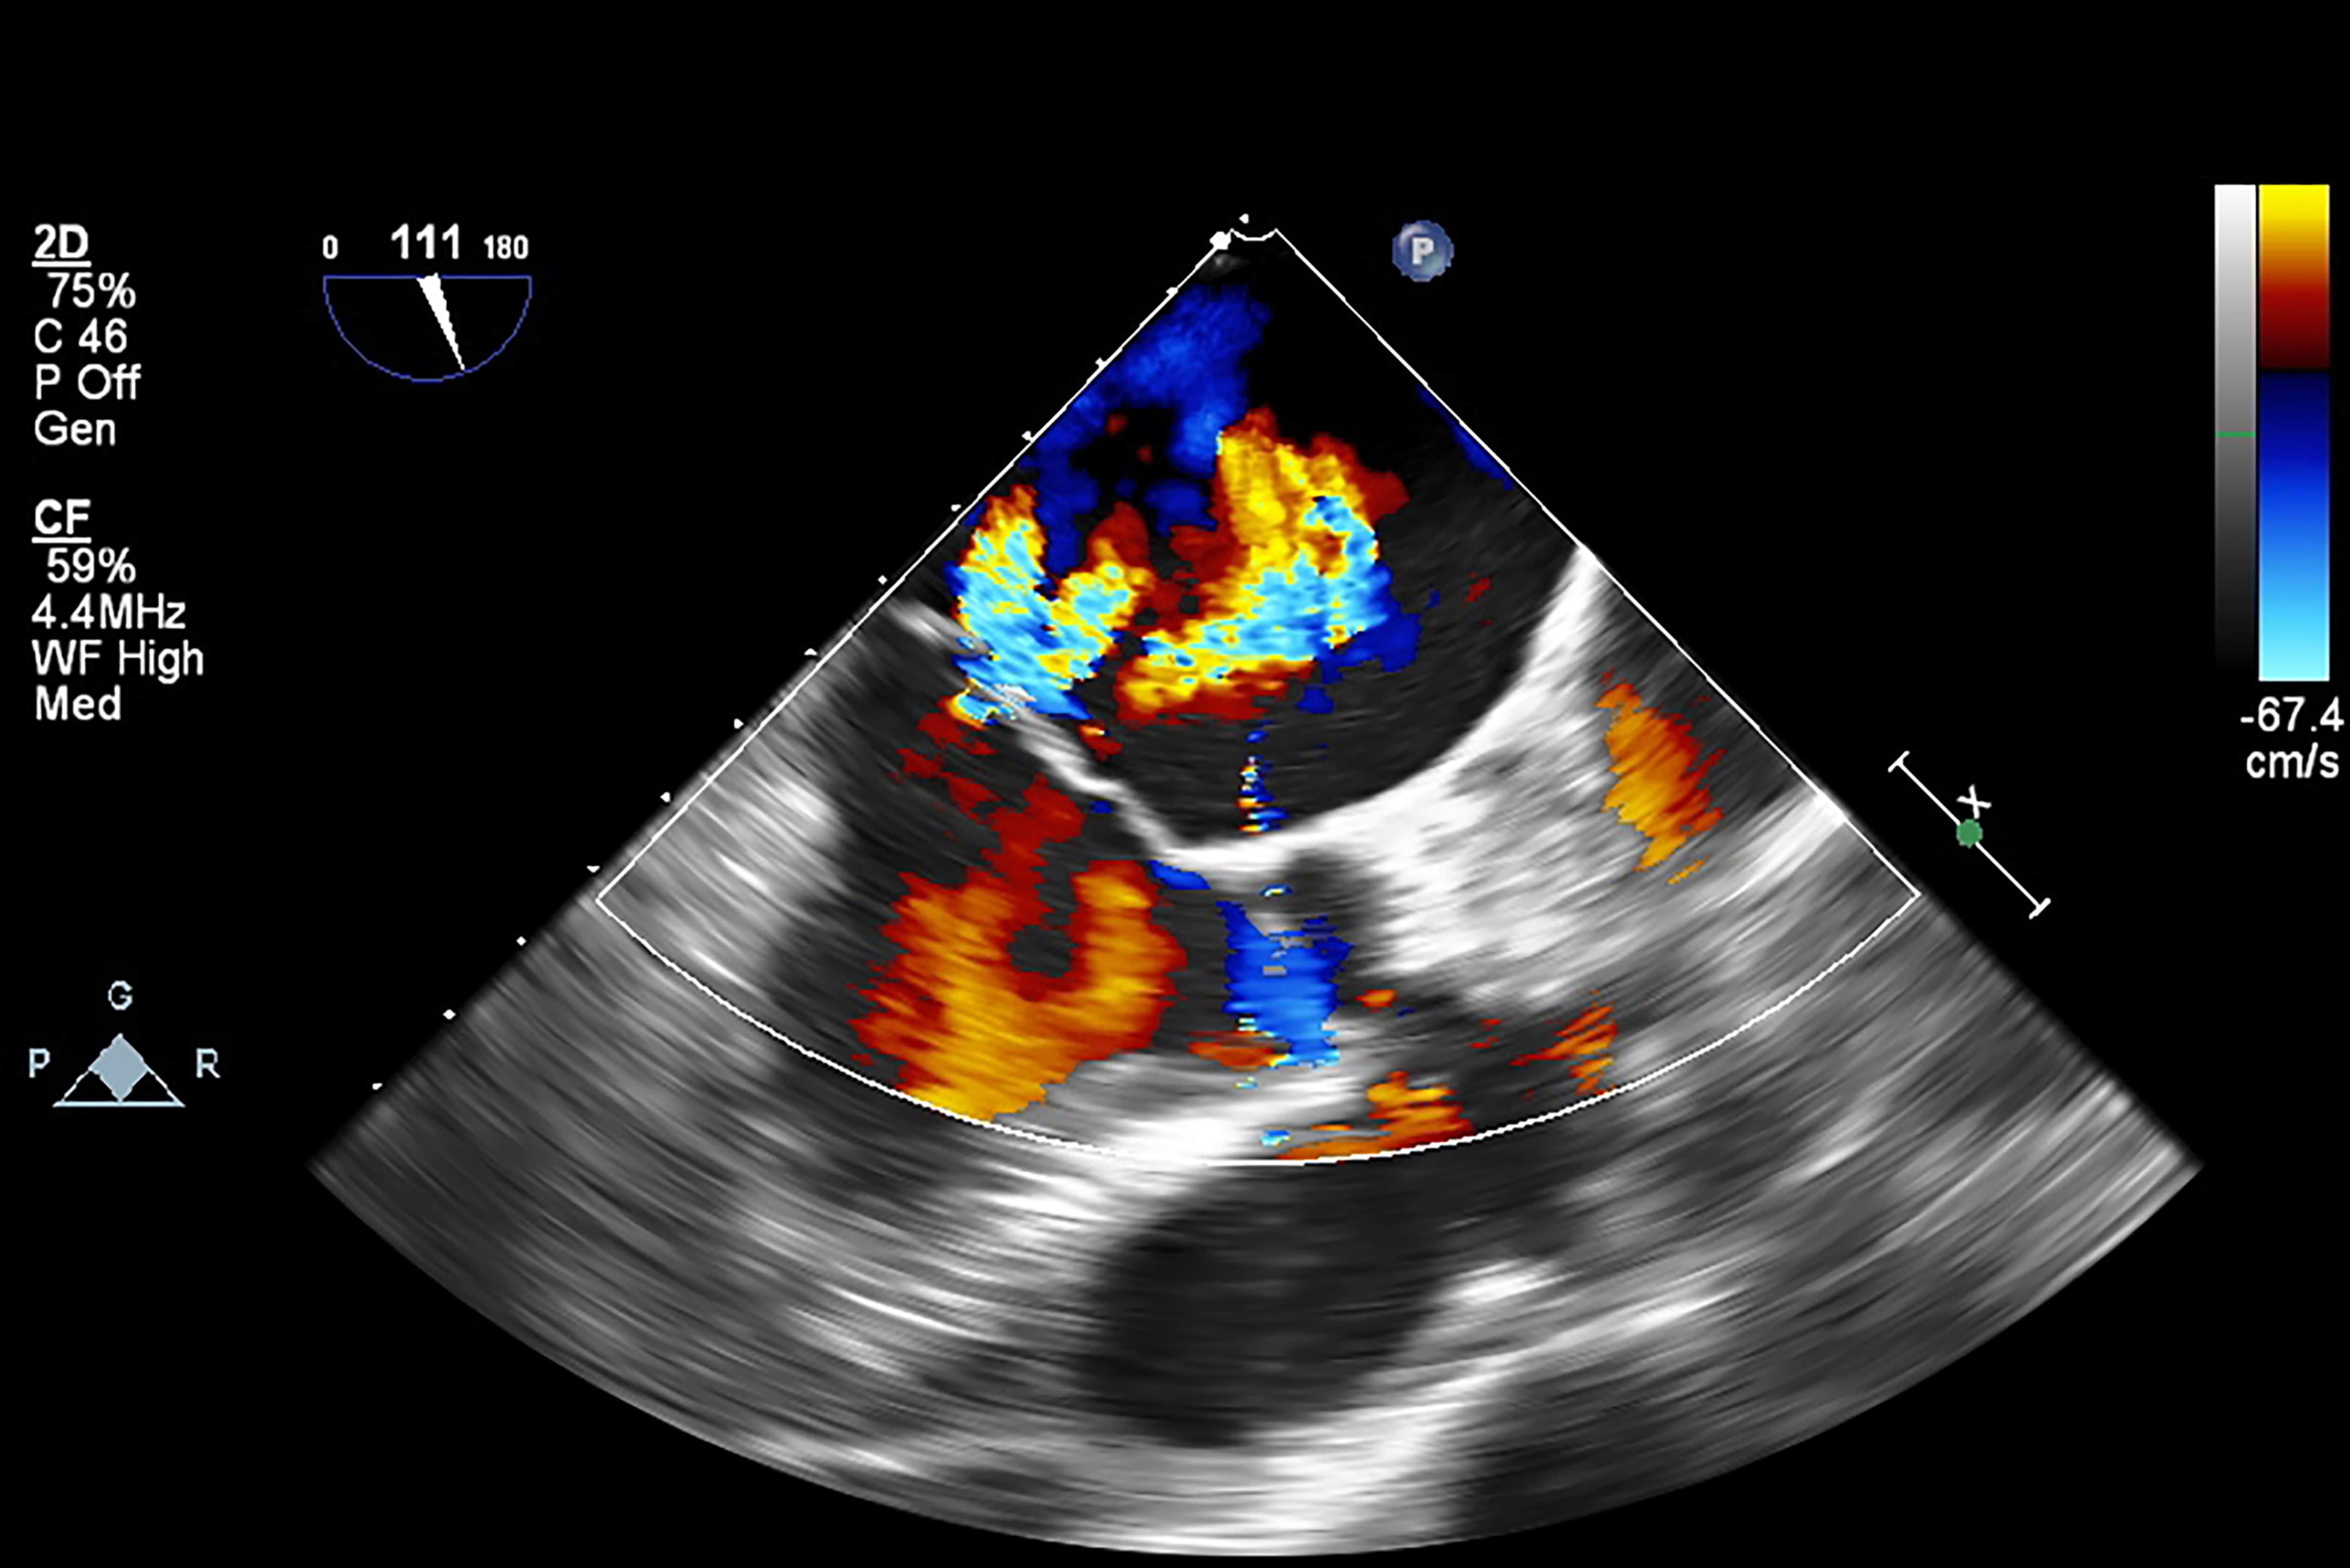

Echocardiography Report Template - It helps assess heart wall thickness (eg, in hypertrophy or atrophy) and. This is done by moving an ultrasound transducer to various locations on your chest, back or abdomen in order to. It looks for patterns to figure out if your heart is. Echocardiography, also known as cardiac ultrasound, is the use of ultrasound to examine the heart. Although it has a similar name, an echocardiogram isn’t the same as an electrocardiogram (ecg), which is a test used to check your heart’s rhythm and electrical. It allows your doctor to monitor how your heart. Echocardiography uses ultrasound waves to create a picture of the heart, which is known as an echocardiogram (echo). It is a noninvasive medical procedure that does not. There are several parts to an echocardiogram. An ekg checks your heart's electrical activity. These images provide pictures of the heart. During an echo, a cardiac sonographer will move a wand across this area. It allows your doctor to monitor how your heart. This is done by moving an ultrasound transducer to various locations on your chest, back or abdomen in order to. Echocardiography uses ultrasound waves to create a picture of the heart, which is known as an echocardiogram (echo). During an echo test, your healthcare provider uses ultrasound (high. It looks for patterns to figure out if your heart is. An echocardiogram is a test that takes moving pictures of the heart with sound waves. The image is called an echocardiogram. Echocardiography, also known as cardiac ultrasound, is the use of ultrasound to examine the heart. It is a type of medical imaging, using standard ultrasound or doppler ultrasound. Echocardiography uses ultrasound waves to create a picture of the heart, which is known as an echocardiogram (echo). During an echo test, your healthcare provider uses ultrasound (high. Your doctor might use this test to look at your heart’s structure and to. Echocardiography, also known as cardiac. It looks for patterns to figure out if your heart is. During an echo, a cardiac sonographer will move a wand across this area. Echocardiography, also known as cardiac ultrasound, is the use of ultrasound to examine the heart. During an echo test, your healthcare provider uses ultrasound (high. An echocardiogram is a test that takes moving pictures of the. Echocardiography uses ultrasound waves to produce an image of the heart, the heart valves, and the great vessels. The image is called an echocardiogram. It is a type of medical imaging, using standard ultrasound or doppler ultrasound. It is a noninvasive medical procedure that does not. Although it has a similar name, an echocardiogram isn’t the same as an electrocardiogram. During an echo test, your healthcare provider uses ultrasound (high. It is a noninvasive medical procedure that does not. It helps assess heart wall thickness (eg, in hypertrophy or atrophy) and. Echocardiography is the study of heart and function using sound waves. There are several parts to an echocardiogram. There are several parts to an echocardiogram. An echocardiogram (echo) is a graphic outline of your heart’s movement. Echocardiography uses ultrasound waves to produce an image of the heart, the heart valves, and the great vessels. An ekg checks your heart's electrical activity. It helps assess heart wall thickness (eg, in hypertrophy or atrophy) and. Your doctor might use this test to look at your heart’s structure and to. During an echo, a cardiac sonographer will move a wand across this area. An echocardiogram (echo) is a graphic outline of your heart’s movement. Echocardiography is the study of heart and function using sound waves. Echocardiography is a test using sound waves to produce live images. It is a noninvasive medical procedure that does not. Echocardiography, also known as cardiac ultrasound, is the use of ultrasound to examine the heart. Your doctor might use this test to look at your heart’s structure and to. An echocardiogram (echo) is a graphic outline of your heart’s movement. The image is called an echocardiogram. An ekg checks your heart's electrical activity. It is a noninvasive medical procedure that does not. Your doctor might use this test to look at your heart’s structure and to. This is done by moving an ultrasound transducer to various locations on your chest, back or abdomen in order to. An echocardiogram (echo) is a graphic outline of your heart’s. An echocardiogram (echo) is a graphic outline of your heart’s movement. An ekg checks your heart's electrical activity. It is a type of medical imaging, using standard ultrasound or doppler ultrasound. It is a noninvasive medical procedure that does not. During an echo test, your healthcare provider uses ultrasound (high. An echocardiogram is a test that takes moving pictures of the heart with sound waves. Echocardiography uses ultrasound waves to produce an image of the heart, the heart valves, and the great vessels. It looks for patterns to figure out if your heart is. During an echo test, your healthcare provider uses ultrasound (high. Echocardiography uses ultrasound waves to create. It looks for patterns to figure out if your heart is. Echocardiography is a test using sound waves to produce live images of your heart. These images provide pictures of the heart. Echocardiography uses ultrasound waves to create a picture of the heart, which is known as an echocardiogram (echo). There are several parts to an echocardiogram. It helps assess heart wall thickness (eg, in hypertrophy or atrophy) and. During an echo test, your healthcare provider uses ultrasound (high. During an echo, a cardiac sonographer will move a wand across this area. The image is called an echocardiogram. Your doctor might use this test to look at your heart’s structure and to. This is done by moving an ultrasound transducer to various locations on your chest, back or abdomen in order to. An ekg checks your heart's electrical activity. It allows your doctor to monitor how your heart. Echocardiography is the study of heart and function using sound waves. Echocardiography, also known as cardiac ultrasound, is the use of ultrasound to examine the heart. Although it has a similar name, an echocardiogram isn’t the same as an electrocardiogram (ecg), which is a test used to check your heart’s rhythm and electrical.Echocardiogram Heart Ultrasound Vs